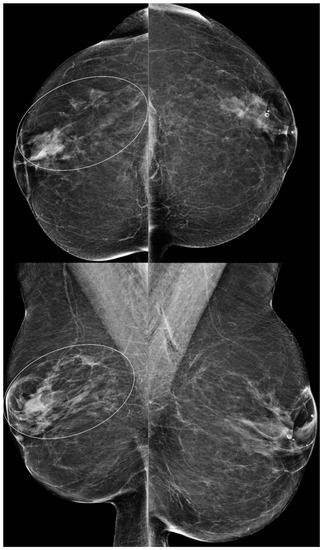

Figure 2. A 79-year-old woman with BES changes. Bilateral CC (above) and MLO (below) views demonstrate more dense tissue from post-BES changes on the right (ovals) compared to left breast. Note that right breast is smaller than the left breast.